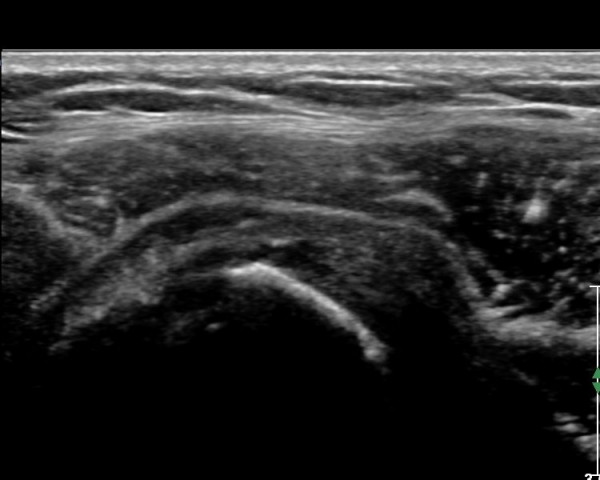

ŽÃËÀÚ¸¦ Á»´õ ¸»´ÜÀ¸·Î À̵¿ ÈÄ(¶Ç´Â ¾Æ·¡·Î ±â¿ïÀÎ ÈÄ) ³»ÃøºÎ¸¦ Á¶ÀýÇÏ´Ï °ß°©ÇÏ±Ù°Ç Ç¥ÃþÀ¸·Î Á¡¾×³¶³» ¼ö¾×Àú·ù°¡ °üÂûµÈ´Ù(»çÁö 3, 4). ŽÃËÀÚ¸¦ Á¶Á¤ÇÏ´Ï ÀÌµÎ¹Ú°Ç ÁÖÀ§ ¼ö¾× Àú·ù¿Í Á¡¾×³¶³» ¼ö¾×Àú·ù°¡ °üÂûµÇ¾î Á¡¾×³¶¿°°ú Ȱ¾×¸·¿°ÀÌ ÀÖÀ½À» ¾Ë ¼ö ÀÖ´Ù(»çÁø 5).